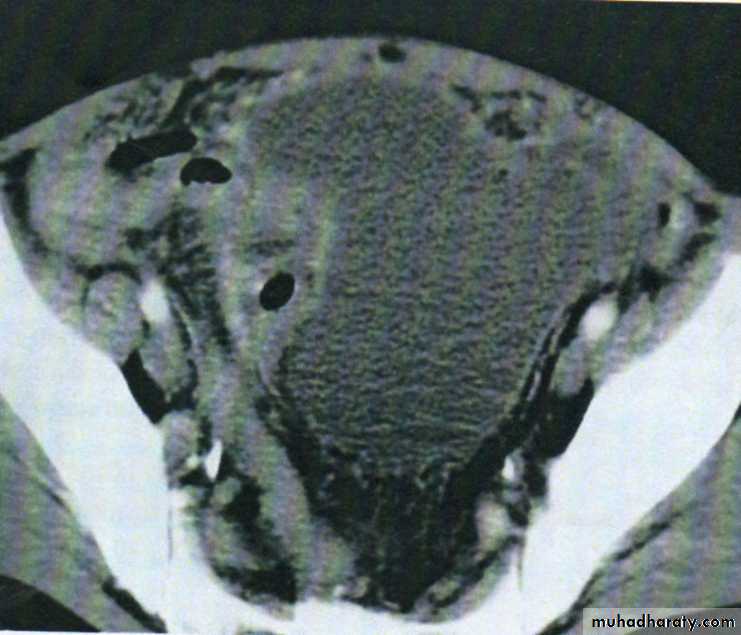

Pelvic abscess

The pelvis is the commonest site of an intraperitoneal abscess because the vermiform appendix is often pelvic in position and the fallopian tubes are frequent sites of infection. A pelvic abscess can also occur as a sequel to any case of diffuse peritonitis and is common after anastomostic leakage following colorectal surgery. The most characteristic symptoms are diarrhea and the passage of mucus in the stools. Rectal examination reveals a bulging of the anterior rectal wall, which, when the abscess is ripe, becomes softly cystic. Left to nature, a proportion of these abscesses burst into the rectum, after which the patient nearly always recovers rapidly. If this does not occur, the abscess is definitely pointing into the rectum, rectal drainage (Fig. 58.6) is employed. If any uncertainty exists, the presence of pus should be confirmed by ultrasound or CT scanning with needle aspiration if indicated. Laparotomy is almost never necessary. Rectal drainage of a pelvic abscess is far preferable to suprapubic drainage, which risks exposing the general peritoneal cavity to infection. Drainage tubes can also be inserted percutaneously or via the vagina or rectum under ultrasound or CT guidance .Al-Madena copy